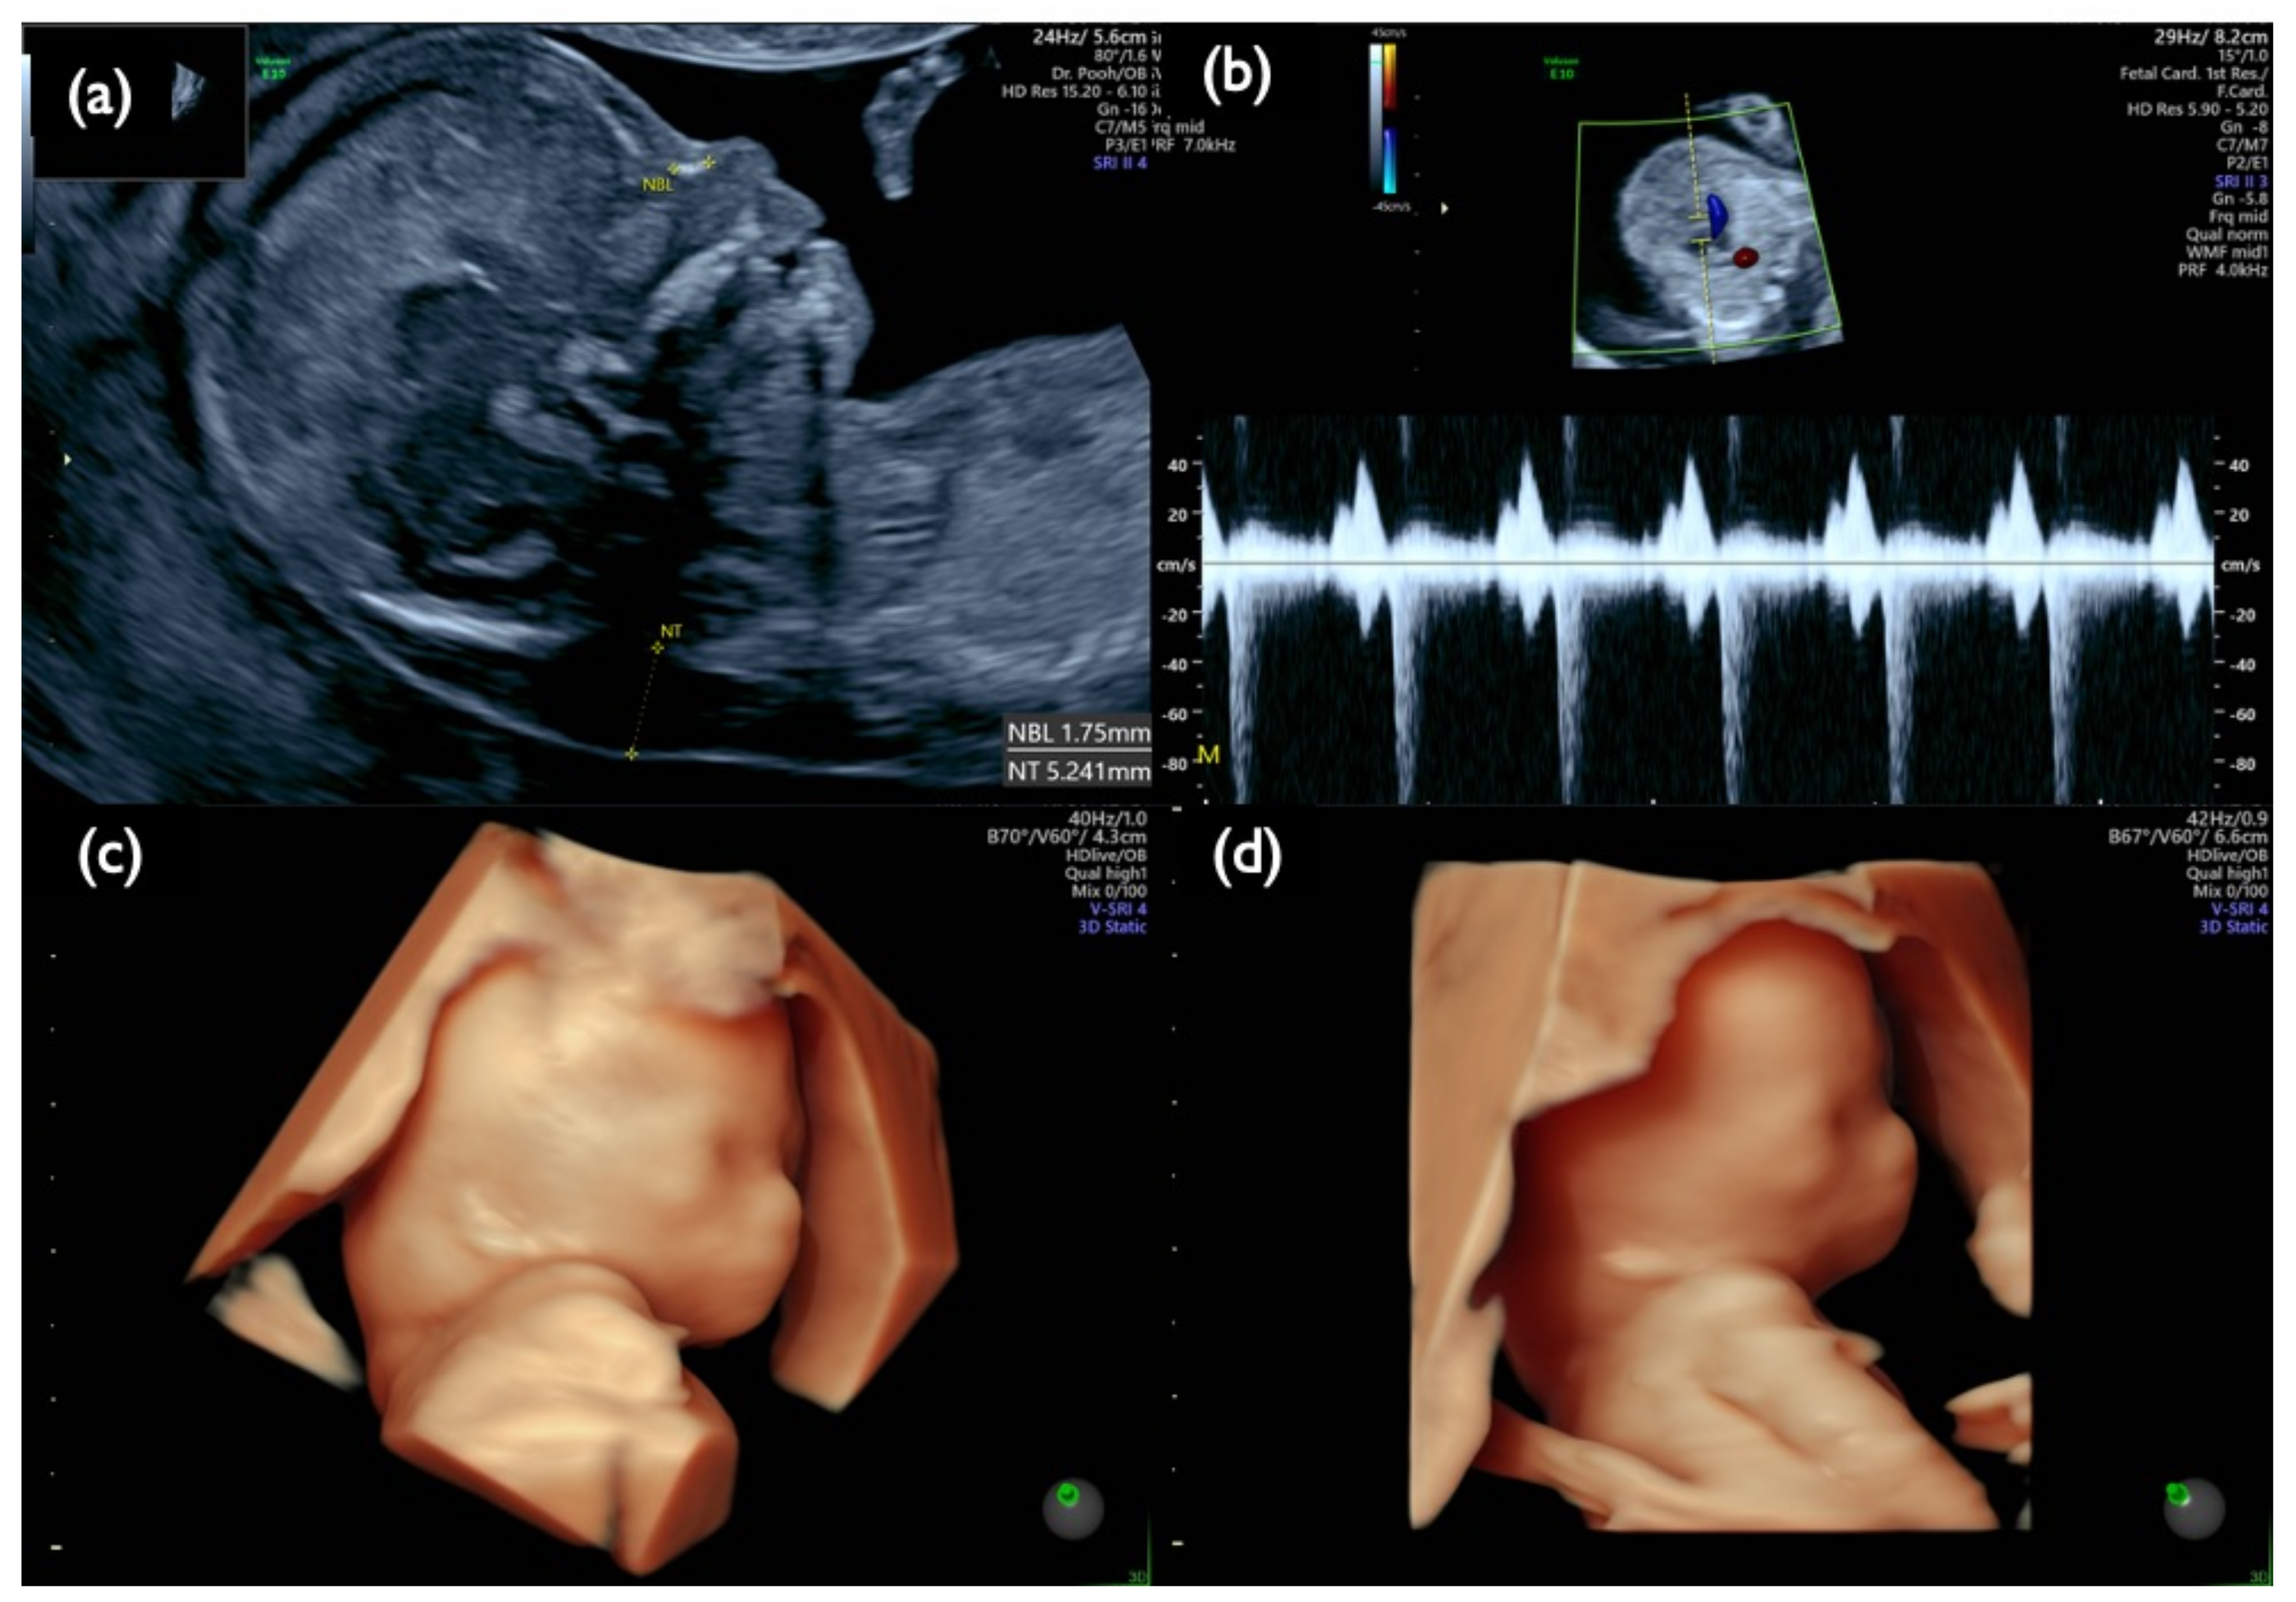

| FP1 | 45,X | T21 positive | 3.55 | MX+ T21 (16%) | MX+D21 | MX+ T21 (8%) | MX+D21 | – | – | MX+ T21 (4%) | 46,XX | CPM | + | 8.8 | Increased NT, CH, General edema, PE bilateral, Small NB, Tachycardia, Short FL/HL, Turner is strongly suspected | |

| FN1 | 47,XY,+21 | T21 negative | 1.07 | – | – | – | – | – | – | – | – | 46,XX | unclear | + | 7.2 | Increased NT, GE mild, NB defect, Lowset ear, TR mild, Small stomach, DV reverse, Tachycardia, T21 is strongly suspected |